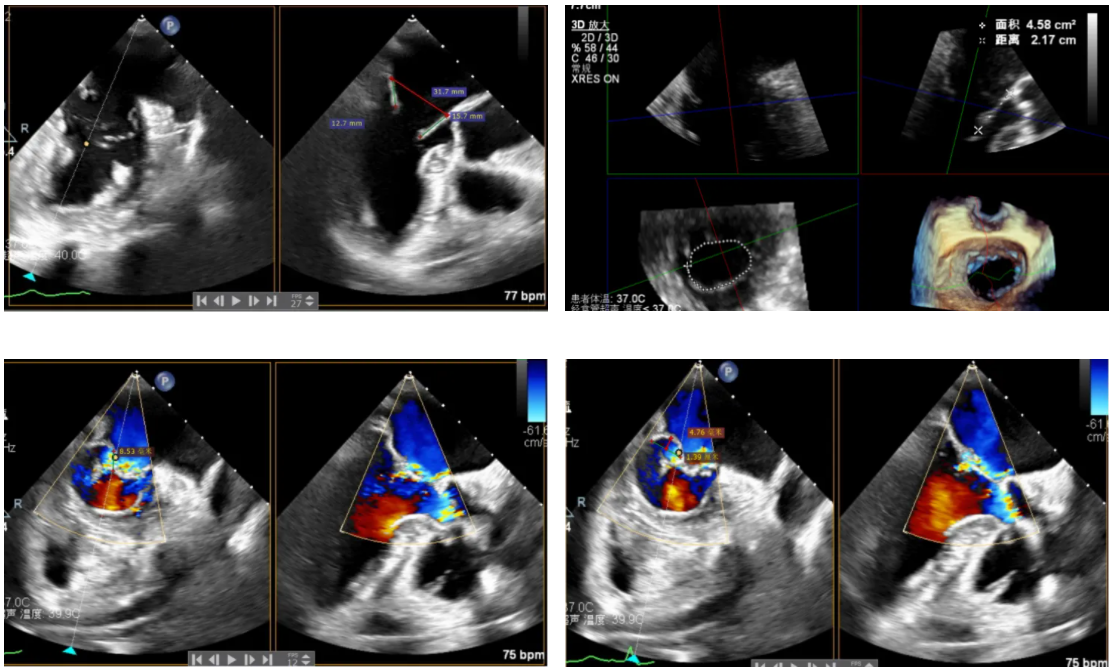

患者为原发性二尖瓣反流(DMR),收缩期可见二尖瓣反流信号,反流位于 2 偏 3 区,基线期二尖瓣反流程度4+。

前叶长度 15.7mm,后叶长度 12.7mm,后叶脱垂宽度13.9mm,脱垂高度4.76mm, 瓣环直径37.1mm,VC:4*7mm, MVA约4cm² 。瓣叶质地较差,腱索断裂、后瓣叶脱垂。

术前超声